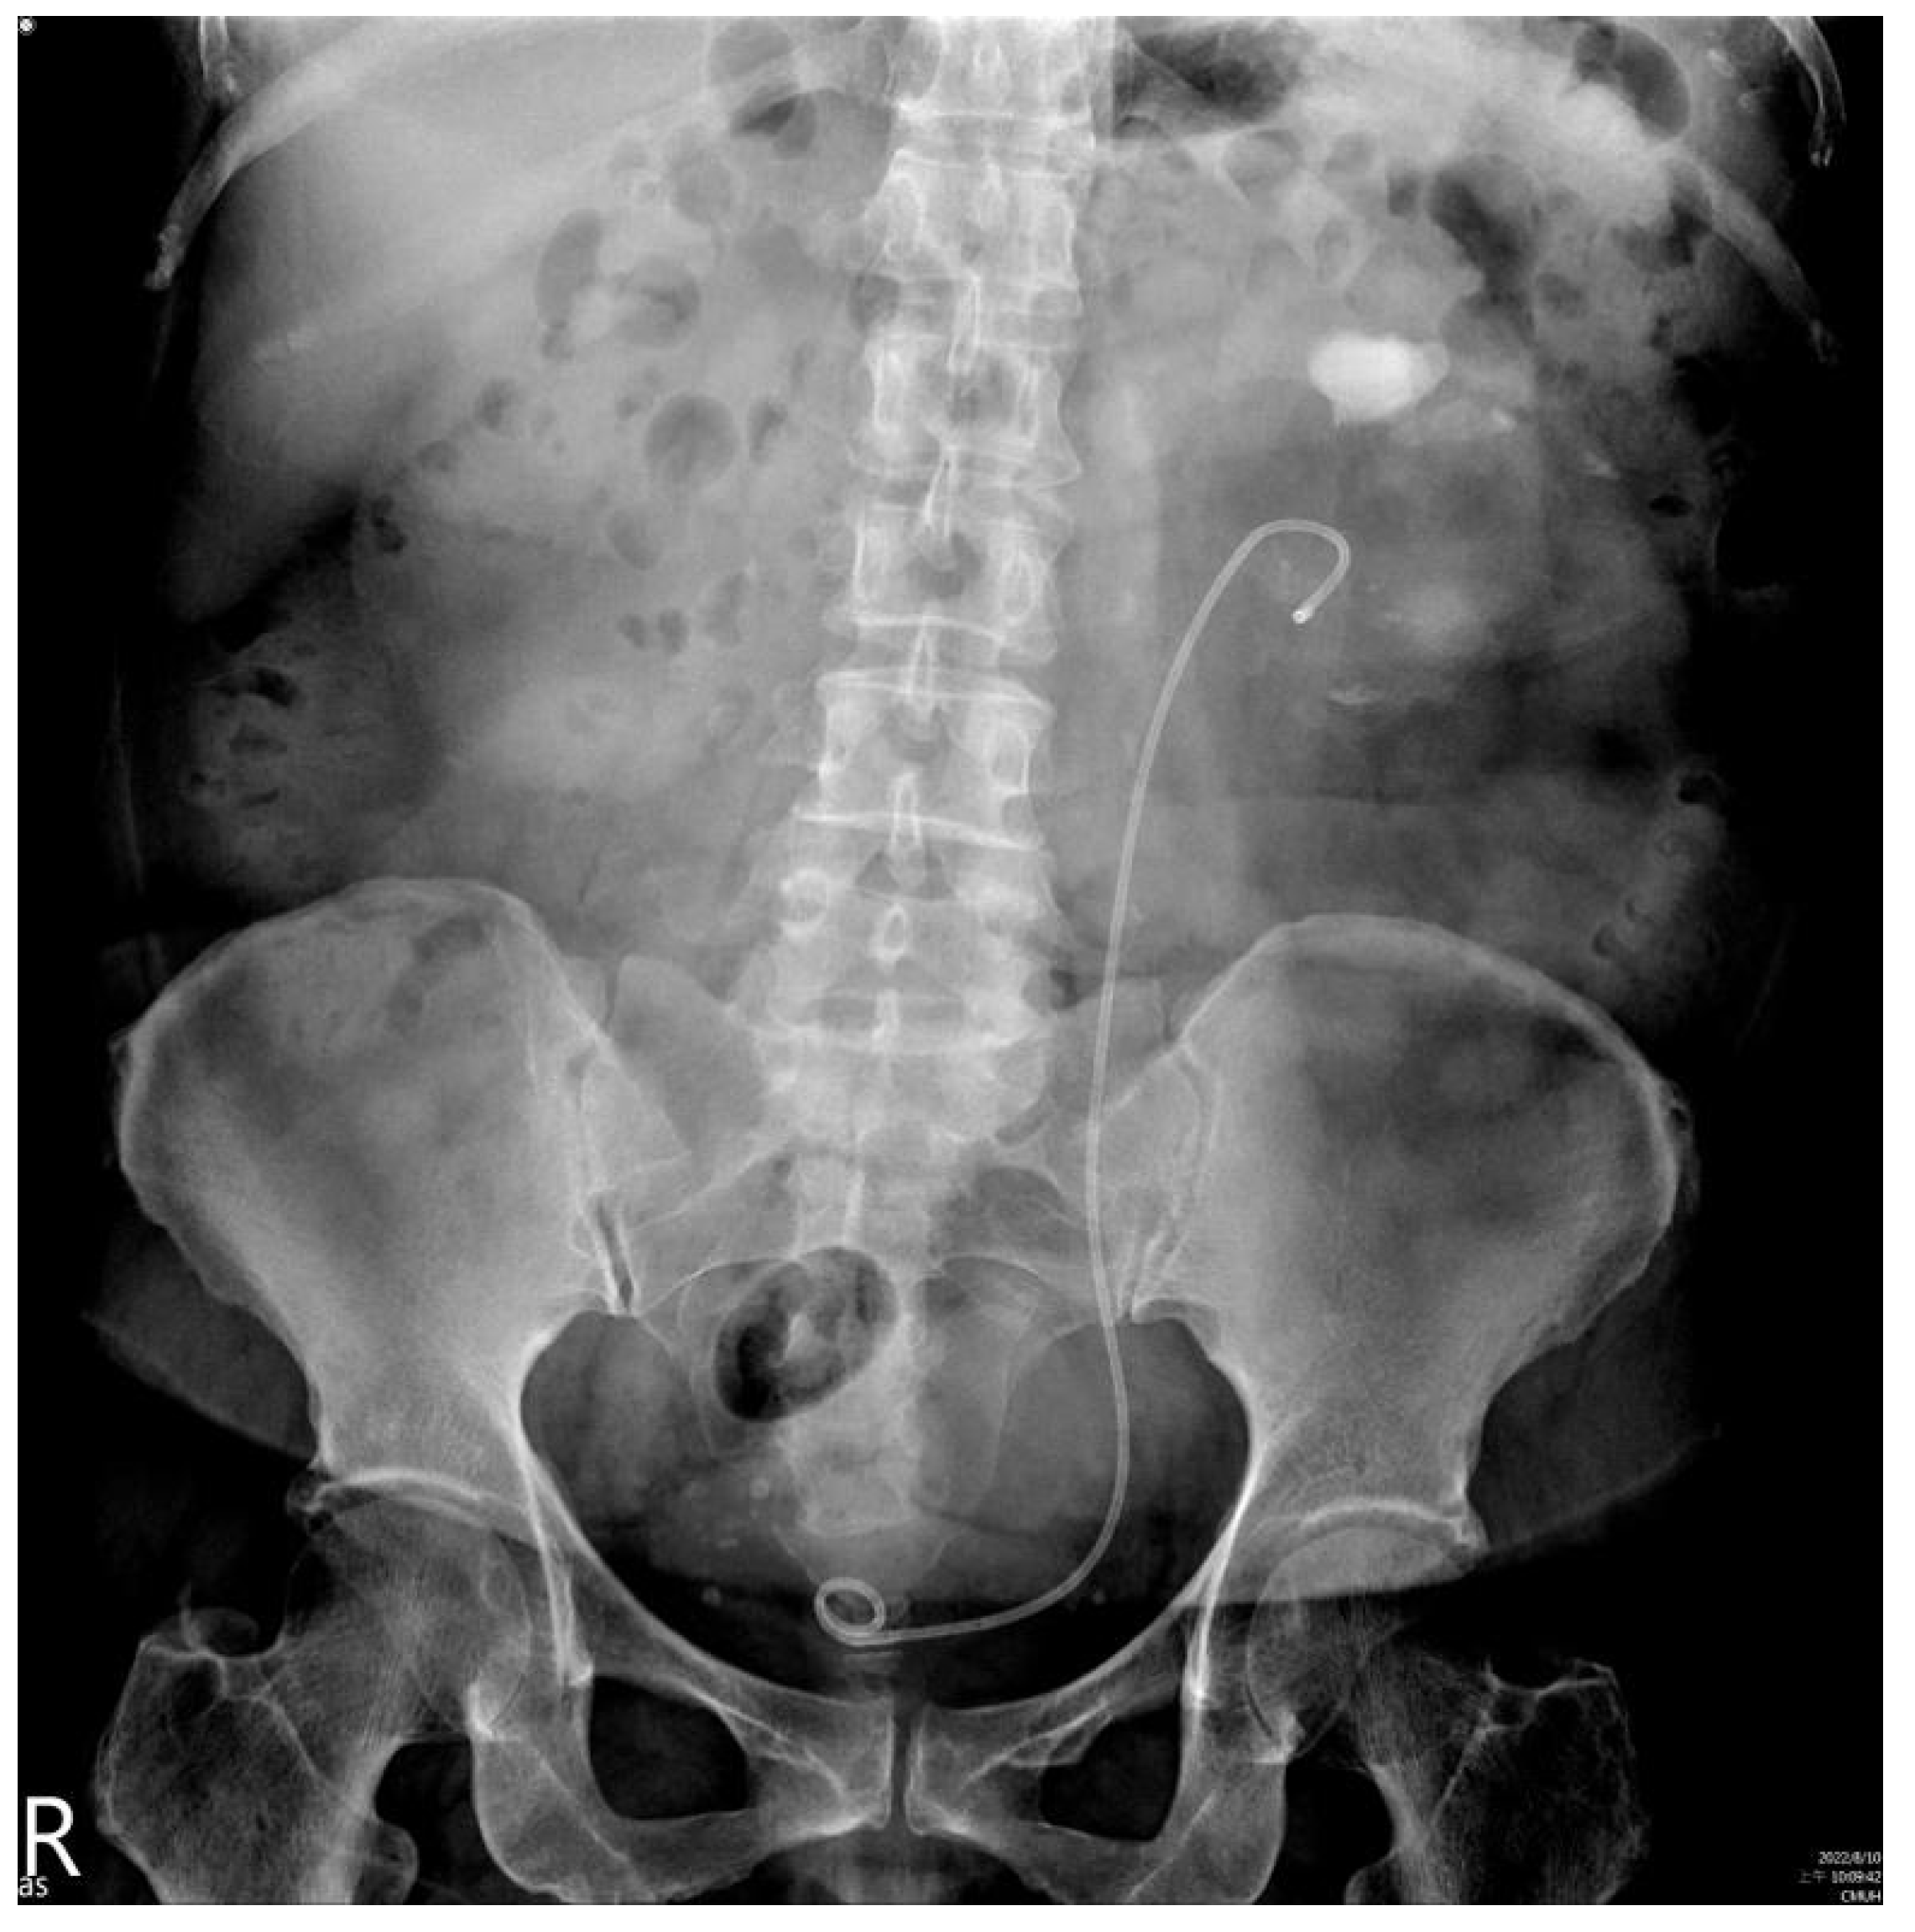

2. Case Presentation